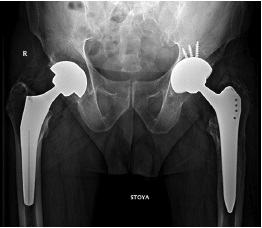

The femoral component was stable, without signs of bone lysis. The component was extracted by traction with a minor effort using an extractor with preliminary use of osteotomes to mobilize it in the proximal part. Its neutral position was registered when assessing the component torsion. Its installation in the retroversion position was revealed during the acetabular component revision, which corresponded to the preoperative X-ray examination findings. The acetabular component was mobilized using an acetabular gouge and removed. The acetabular contours were preserved, without wall defects. The repeated maximum total synovectomy was performed, followed by the use of the Pulsavac (Zimmer) pulse system to remove ceramic fragments using a water jet. Hemostasis control was performed. A mixed fixation femoral component (Alloclassic) and an acetabular press-fit fixation component (Continuum), as well as Ce-Ce tribological bearings (Biolox Delta), were chosen for the revision replacement of the femoral component. A 62-mm continuum acetabular component due to revision arthroplasty, which was fixed with three screws after impaction, and a 62/36 mm ceramic liner, were installed. The femoral component No. 9 (Alloclassic) was installed, considering the correction of the varus position of the previous component with installation along the medullary canal axis. The 36 mm + 7 XL ceramic head was chosen for limb length correction. The femoral component was repositioned into the endoprosthesis cup after the head was installed. Their sufficient volume was revealed when testing movements in the left hip joint. Additionally, the surgical wound was sanitized using the Pulsavac system with 1 L of normal saline solution. Finally, the wound was sutured in layers with Vicryl. Staples on the skin and an aseptic dressing were used. The wound healed by primary intention. The patient was discharged on day 10. The plain radiography of the pelvis in the antero-posterior view determined that the acetabular component inclination was 35°, the femoral component was in the correct position when conducting control 3 months postoperatively, and no valgus or varus angulation was noted (Fig. 6). MSCT in the axial projection revealed that the acetabular component was implanted in the anteversion position of 17° (Fig. 7).

Fig. 6. Anteroposterior X-ray view of the pelvis 3 months after surgery: on the right — a total hip replacement with a cementless proximal fixation (2019); jn the left — a total hip replacement with a cementless proximal fixation

Fig. 7. MSCT of pelvis in axial projection: anteversion of acetabular component 17°